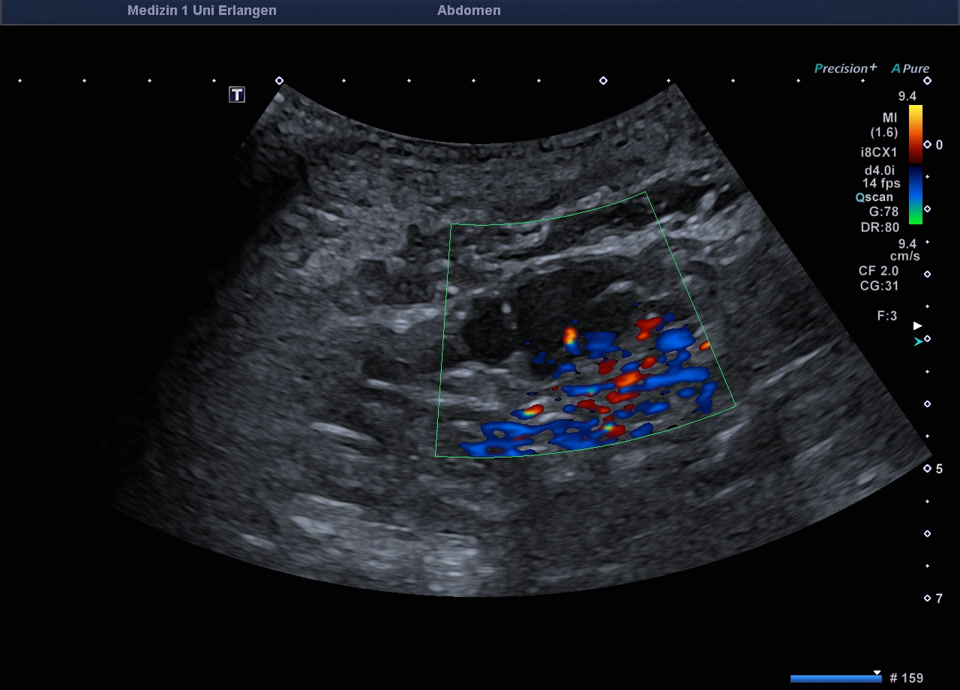

• Bosniak IV cyst (color doppler)

• Bosniak III cyst in the left kidney (color Doppler)